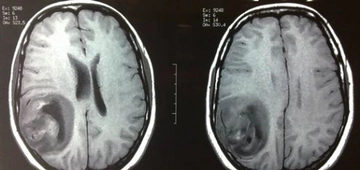

Annemin kafasında tmör var dedi doktoru kötü huylu mu iyi huylumu bioksi sonucunu bekliyoruz kafa da iyi huylu da çıkabiliyor mu parça almadan önce kafa ağrısı vardı annemde alınalı on gün oldu kafa Ağrı sı yok ne yapacağımızı bilemiyoruz bize yardımcı olabilirmisiniz

Hüsnü bey merhabalar iyi günler dilerim. Kafa dediğiniz kısmı sanırım beyin olarak düşünüyorum. Bu bölgede çıkan tümörler, benign olarak adlandırılan iyi tümörler de olabilir; malign adı verilen kötü huylu tümörler de olabilir. Bunu anlamanın en iyi yolu biyopsi sonucunu beklemektir. Çıkan sonuca göre, doktorunuz uygun bir tedavi planı oluşturacaktır. Sağlıcakla...

Merhaba Hüsnü Bey, meydana gelen kistler kötü huylu da olabilir iyi huylu da. Bu tamamen gelecek olan biyopsi sonucunda karşımıza çıkacaktır. Bu nedenle sabırla beklemekte fayda vardır. Ameliyatlı olan noktanın enfeksiyon kapmaması için şuan buna odaklanıp iyi bir bakım yapmanız tavsiye edilmektedir.